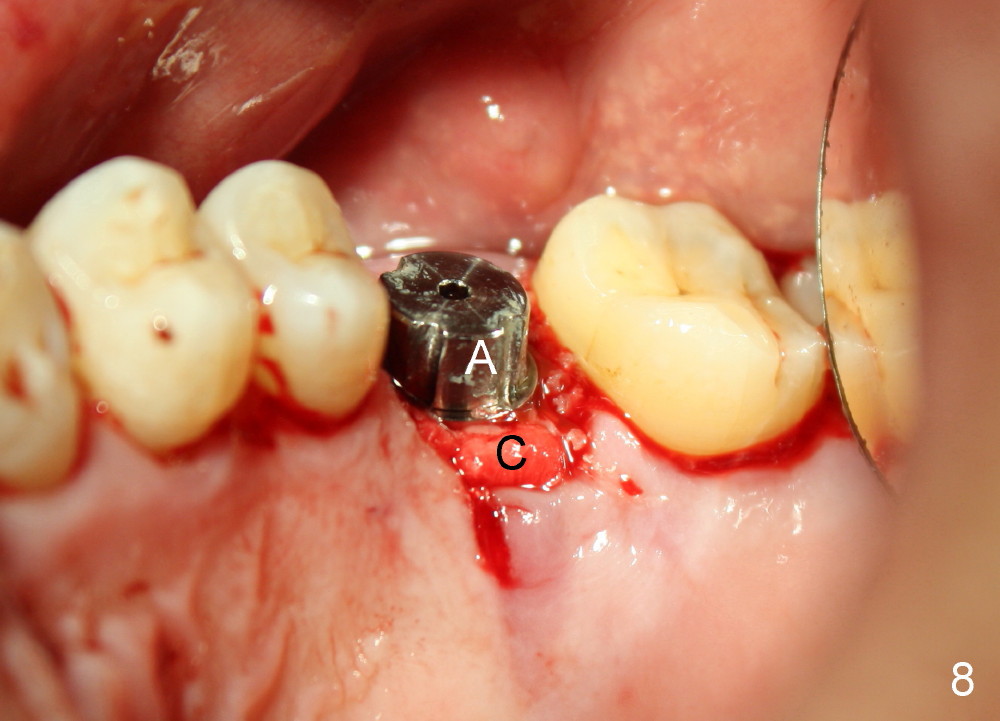

Bone density around the molars (including apical to #14) (Fig.1 black *) is higher than that around the premolar (white *). In fact the tooth has horizontal root fracture (Fig.2: <: CEJ), consistent with high bone density (strong mastication). An immediate implant is planned (Fig.3). After extraction, osteotomy starts at the buccal slope of the palatal (Fig.4 P) socket. Because of high bone density apical to the sockets, drills are required for osteotomy in the septum (type II bone) instead of osteotomes and primary stability is easily achievable (>60 Ncm). When a 7 mm implant (Fig.6 I)) is placed, the peri-implant gaps are much smaller (*) than that with a 4.5 mm tap (Fig.5 T). This helps bone grow faster toward implant. A long implant (17 mm) is necessary for this case to obtain primary stability in the apical one (double arrows in Fig.6). With reamers, a fair amount of autogenous bone is harvested during drilling, mixed with allograft and synthetic bone and placed in the remaining buccal (Fig.7) and palatal (Fig.8) sockets. The openings of the buccal and palatal sockets are covered with collagen dressing (C) and perio dressing. The latter is kept in place by a short abutment (Fig.6-8 A).